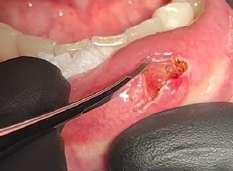

Il mucocele del cavo orale è la seconda lesione più comune. Nella fascia di età compresa tra 10 e 29 anni, il tasso di incidenza è più elevato. Il mucocele è caratterizzato da un accumulo di mucine. Ha una forma a cupola. Di solito hanno un colore bluastro. Il

mucocele si trova più comunemente sul labbro inferiore, seguito dalla mucosa buccale e dal pavimento della bocca. L'incisione tradizionale con bisturi e/o l'escissione chirurgica, la marsupializzazione, la micromarsupializzazione, l'iniezione di corticosteroidi, l'agente sclerosante, la criochirurgia, l'elettrochirurgia e il laser sono tutte procedure validate per il trattamento del mucocele in letteratura.

I laser a diodi forniscono una guarigione delle ferite e un tasso di recupero più rapidi rispetto ai loro rivali. Grazie alle sue

qualità antibatteriche e antinfiammatorie, questa terapia laser ha l'ulteriore vantaggio di migliorare la guarigione delle ferite senza infezioni o edema.

Le procedure laser-assistite sui tessuti molli presentano i vantaggi di un minimo sanguinamento intraoperatorio, edema e dolore postoperatorio, oltre a tempi chirurgici, cicatrici e coagulazione minimi.

La dimensione di un sito chirurgico determina se vengono utilizzate o meno le suture. Le procedure che comportano un'escissione piccola o significativa dei tessuti molli, l'esposizione dell'impianto con o senza taglio osseo, possono essere eseguite in pazienti con problemi di sanguinamento.

Questo caso è coerente con precedenti segnalazioni di escissione del mucocele utilizzando un laser a diodi.

L'enorme quantità di tessuto rimosso e il livello di comfort del paziente supportano ulteriormente il fatto innovativo che può essere utilizzato anche per il mucocele di grandi dimensioni.

I mucoceli della mucosa orale sono malattie tumorali benigne delle ghiandole salivari minori della mucosa orale. Si verificano più comunemente nella mucosa labiale. Possono essere causate da una rottura dell'epitelio della ghiandola che secerne saliva nello spazio extraghiandolare e forma una pseudocisti (mucoceli da stravaso) oppure da un blocco del flusso salivare dovuto ad una proliferazione epiteliale del dotto escretore che forma una cisti salivare (cisti da ritenzione).